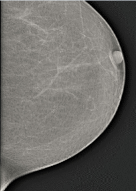

The dataset was mainly collected from St.Gebriel Hospital, Grum Hospital, Betezatha Hospital, Korean Hospital, Kadisco Hospital and Pioneer Diagnostic. The MG images were collected with their document reports that show the screening and diagnosis results of the patients. The documents report results were based on the pathology confirmation and Breast Imaging-Reporting and Data System (BI-RADS). More than 5000 x-ray mammogram images that were diagnosed between 2016 and 2018 as shown in table 1 were collected and some of the samples are shown in figure 1. This work considered only the mass abnormality from the collected MG images, that is 1588 full mammogram images which have mass abnormality and annotated by professional radiologists using the labelMe Russell et al. (2008) annotation tool. The dataset was divided into training (80%), validation (10%), and testing (10%).

Refer to caption

(a)

(b)

(c)

Figure 1: Sample of MG images during acquisition stage. The mammogram images are from different mammography x-ray sources: (a) from Girum Hospital, (b) from Pioneer Diagnostic Center, and (c) from St. Gebriel Hopital.